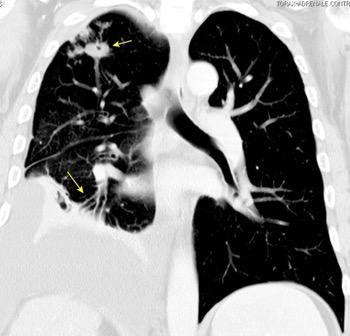

Engrosamiento de la pleura parietal 36/ 59 exudados (61%) 56% de D. paraneumónicos 100% de empiemas Especificidad.. 96%.

Exudado versus trasudado.

Aquino SL, et al. Pleural exudates and transudates: diagnosis with contrast-enhanced CT. Radiology 1994

Signo de la Pleura separada “Split pleural sign”

Capas pleurales de grosor uniforme realzadas por el contraste

No específico de empiema. Indica “exudado”. 68% de pacientes con empiema pleural.

Capas pleurales de grosor uniforme

Realce grasa extrapleural (30%)

> Grasa Extrapleural. (60-80%)

Kraus GJ. Split pleural sign. Radiology 2007

Pleural visceral 50%

Pleural parietal 100%

Walker CM et al. Imaging Pulmonary Infection: Classic Signs and Patterns. AJR. 2014/Stark DD, et al. Differentiating lung abs cess and empyema: radiography and computed tomography. AJR. 1983